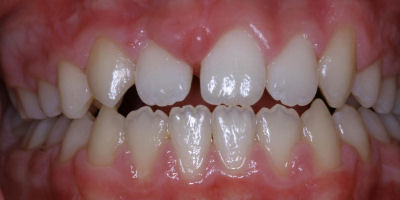

Repair Worn Teeth